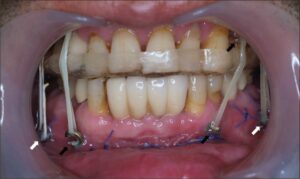

البراغي الجراحية أصغر بكثير من زرعات الأسنان. يبلغ طولها أحياناً بضعة ميليمترات فقط. وظيفتها هي مجرد الحفاظ على قطعتي العظم بجوار بعضهما وليست تثبيت الأسنان الاصطناعية. لذلك بعد العملية لن ترى أي معدن في فمك وتكون كل هذه الوصلات مخفية تحت نسيج اللثة.

القلق بشأن الإحساس بالبراغي تحت الجلد هو أيضاً في أغلب الأحيان في غير محله، فسماكة هذه الصفائح ورؤوس البراغي قليلة جداً. إلا في مناطق خاصة مثل تحت العين أو جوانب الأنف حيث الجلد رقيق جداً، فهناك احتمال للمسها. في النقاط الأخرى تغطيها أنسجة الوجه والعضلات تماماً ولن تلاحظ وجودها إطلاقاً.